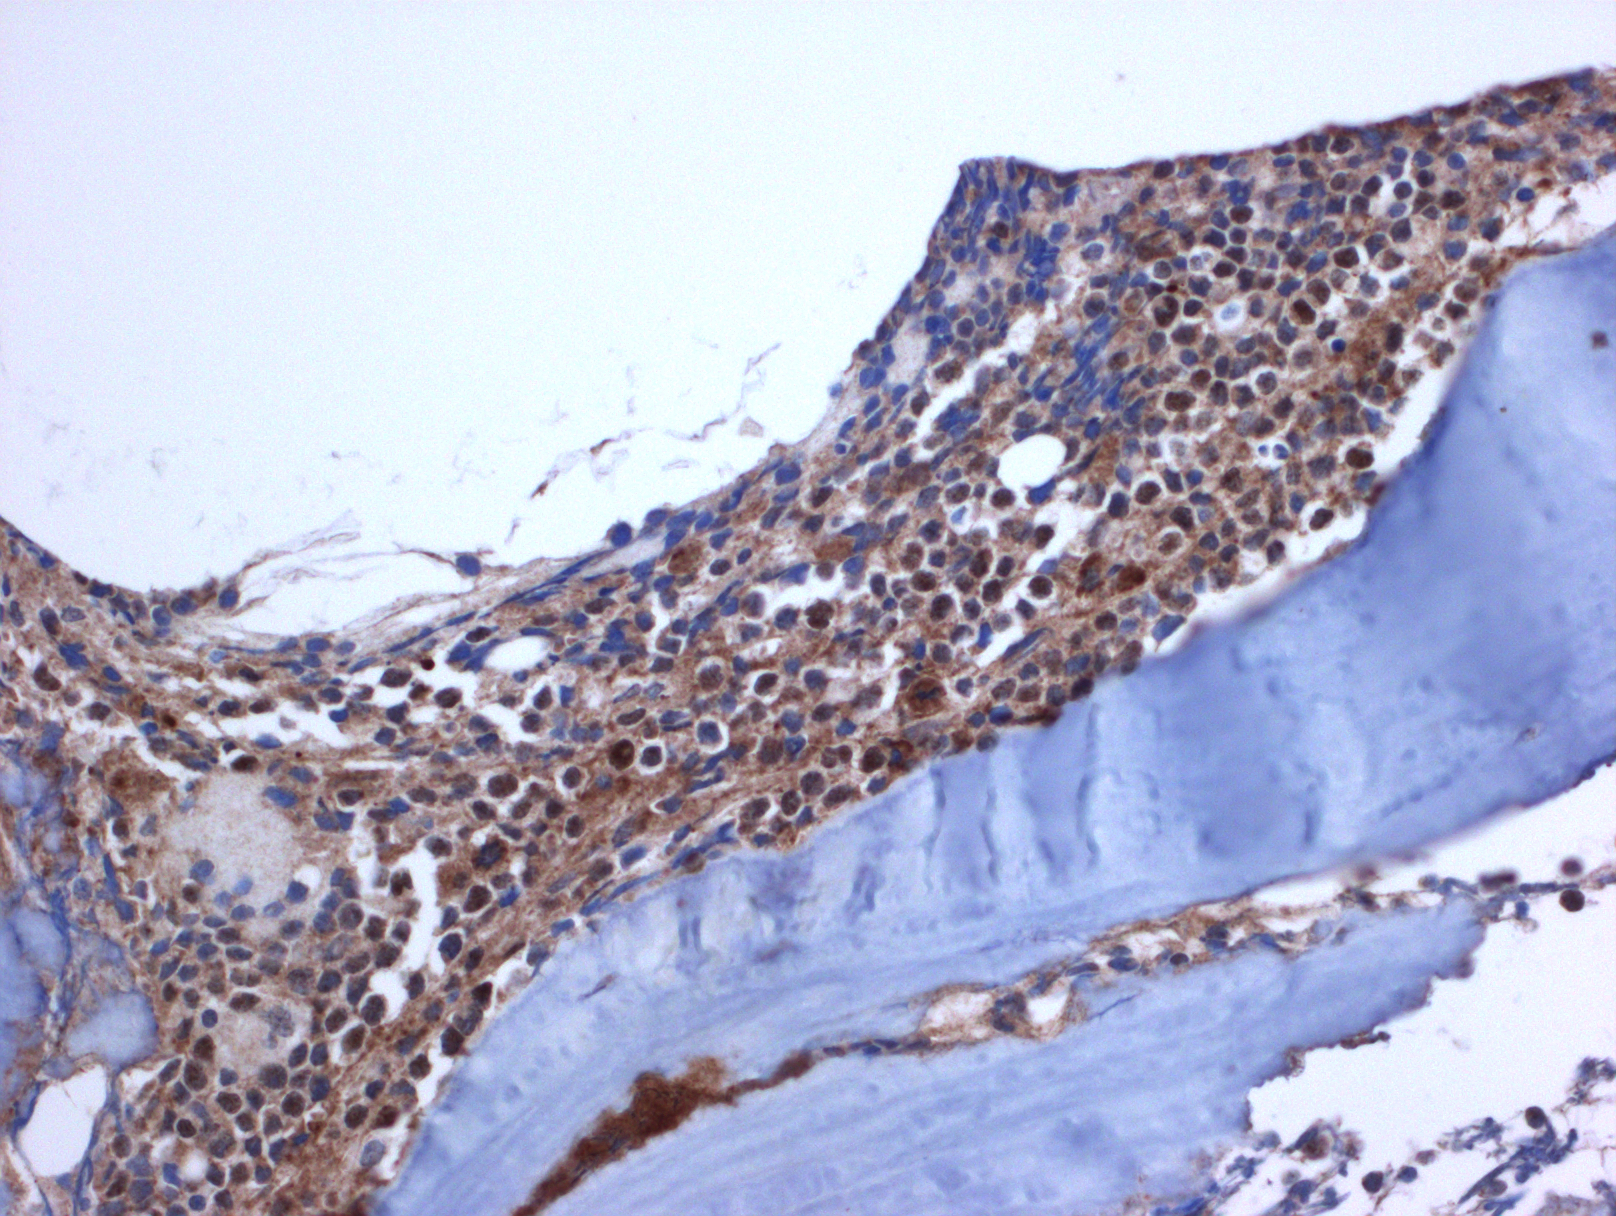

- 免疫表型: T-ALL/LBL 中淋巴母细胞呈 TdT 阳性,可表达 CD1a、CD2. CD3. CD4. CD5. CD7 和 CD8 中的一种或多种,最常见的是 CD7 和胞浆 CD3ε 阳性表达,其中只有 CD3 具有确定肿瘤细胞来源的特异性。CD4 和 CD8 常有合表达,CD10 也可以阳性;但这些都不具特异性。不成熟抗原除 TdT、CD1a、CD34 外,CD99 的表达也可表明其前体细胞的特性。部分病例表达 TAL1(核染)。偶有病例 CD117 阳性(常伴有 FLT3 突变)。10%病例表达 CD79a,少数可以表达 CD13 和/或 CD33。根据分化阶段不同,可将 T-ALL 分为以下几型:原 T(Pro-T):cCD3+、CD7+、CD2-、CD1a-、CD34-/+、CD4-、CD8-;前 T (Pre-T):cCD3+、CD7+、CD2+、CD1a-、CD34+/-、CD4-、CD8-;皮质 T(cortical T):cCD3+、CD7+、CD2+、CD1a +、CD34-、CD4+、CD8+;髓质 T(medullary T):cCD3+、CD7+、CD2+、CD1a-、CD34-、sCD3+、CD4 或 CD8 阳性。前两型中的很多病例符合 WHO 2017 年版分类中的早期前 T 淋巴母细胞白血病 (见下)。

胸腺瘤或异位胸腺 :淋巴细胞和上皮细胞两种混合成分。淋巴细胞无异型性,TDT+;其混合相间的胸腺上皮(正常形态—异位,异型-肿瘤)CK+。